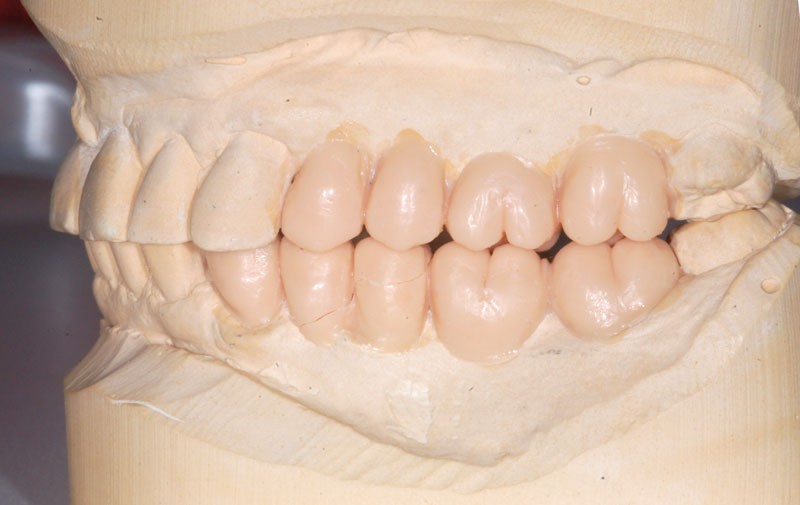

Le modèle de travail est fabriqué au laboratoire, des piliers CFAO Atlantis™ sont réalisés en fonction du bridge antagoniste transitoire.

Le bridge 24-26 céramométallique et la couronne unitaire sur 27 sont réalisés. Les piliers CFAO sont transvissés sur les implants, puis les éléments céramo-métalliques sont posés. Le résultat montre un parfait respect du projet prothétique en fonction de la courbe occlusale obtenue avec le bridge transitoire réalisé avec le ProtempTM 4 et une adaptation parfaite.